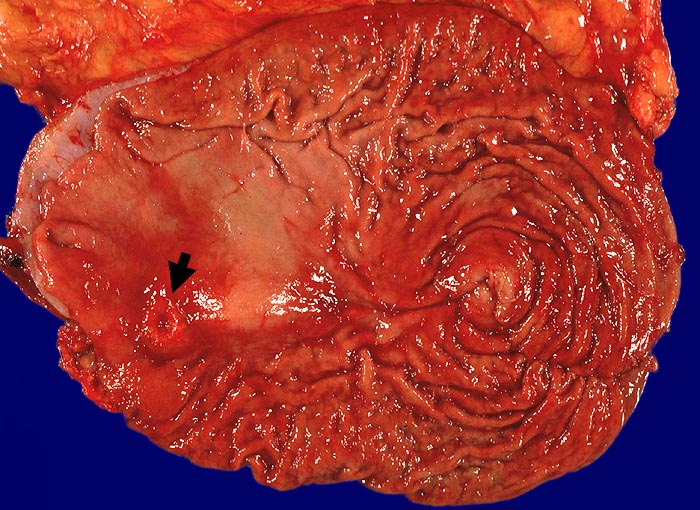

Neuroendokrines Karzinom

Magen

Im Bereich des Magenantrums, 3cm vom distalen Resektionsrand entfernt, ein schüsselförmig exulzerierter ► Tumor, Dm 1,2cm.

pT3, G1. Neuroendokrines Karzinom vom trabekulären und alveolären Subtyp.